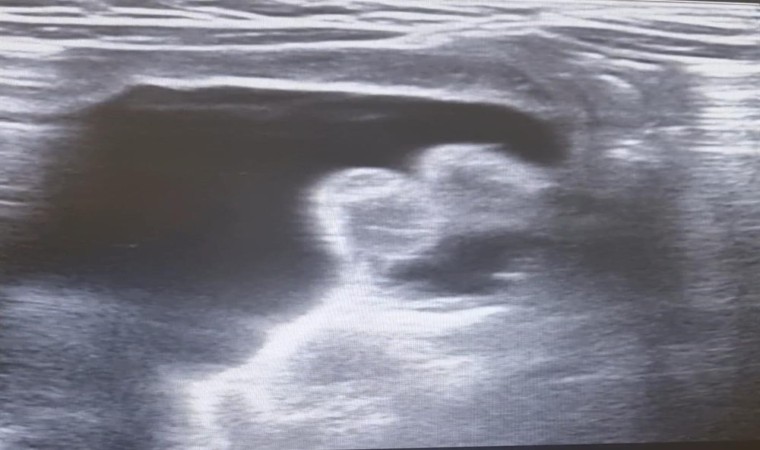

Edinilen bilgilere göre, kanlı ishal ve genel durum bozukluğu nedeniyle Hitit Üniversitesi Erol Olçok Eğitim ve Araştırma Hastanesi’ne kaldırılan 9 aylık bebeğe halk arasında "bağırsak düğümlenmesi’’ olarak bilinen invajinasyon tanısı konuldu. Yapılan değerlendirmeler neticesinde invajinasyonun düzeltilmesi için transrektal yoldan işlem yapılması kararı alındı. Radyoloji Kliniği Eğitim Görevlisi ve Çocuk Radyolojisi Uzmanı Doç. Dr. Altan Güneş ve Çocuk Cerrahisi Kliniği Eğitim Görevlisi Prof. Dr. Çağatay Evrim Afşarlar tarafından acil serviste bebeğin düğümlenen bağırsağı ameliyata ihtiyaç kalmadan tedavi edildi.

Konu hakkında bilgi veren Çocuk Radyolojisi Uzmanı Doç. Dr. Altan Güneş, “İnvajinasyon veya halk arasındaki adıyla barsak düğümlenmesi, çocuk hastalarda sık görülen, erken tanı ve tedavi gerektiren, genellikle kanlı ishal, karın ağrısı ve genel durum bozukluğu gibi şikayetlerle hastaneye başvuru sebebi olan, tedavi edilmediği takdirde barsak delinmesi, barsak kaybı ve ağır vakalarda ölüme kadar gidebilecek ciddi bir acil durumdur. Tedavisinde ameliyata alternatif seçeneklerden birisi olarak ultrasonografi eşliğinde redüksiyon seçkin merkezlerde uygulanan bir tedavi yöntemidir. Bu sayede hastaların hastanede kalış süresi azalmakta, hastalar cerrahi yöntemlerin olumsuz yan etkilerinden korunmakta ve hızla, bazen aynı gün iyileşebilmektedirler’’ dedi.